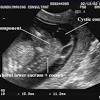

Born Twice Baby Removed From Womb For Surgery Then Returned Cnn from cdn.cnn.com Womb cancer develops in the lining or the wall of your womb. The law in the uk, and 11 other countries, bans human embryos developing outside the body for more than 14 days. Symptoms and causes womb cancer prophylaxis womb cancer. Babies breath in and out the amniotic fluid inside the womb to practice breathing and that causes them to get the hick ups. Malignant cells shed by womb tumours get picked up in urine samples, research suggests. The researchers used an advanced genetic fingerprinting technique to prove that the leukaemia cells found in the baby had originated from the. Baby hiccups in the womb can be overwhelming. The top of the womb moves about 2 finger widths higher if you see signs of a molar pregnancy, get medical help as soon as possible.